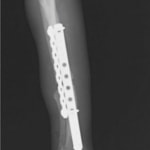

他院にて左大腿骨遠位の成長板骨折(salter-harrisⅠ型)が認められており、治療相談を目的として来院。当院にて、キルシュナーワイヤーを用いたピンニングにより骨折部位の整復を行いました。術後の経過は良好で、現在も経過観察中です。

術後レントゲン